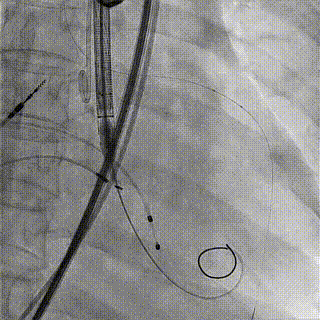

术中影像

1.主动脉根部造影,可见大量反流

2.输送系统过主动脉弓

3.输送系统造影定位

4.释放瓣膜

5.瓣膜完全释放

6.最终造影,反流消失

手术结果

术后食道超声及造影未见瓣周漏,效果良好,手术圆满完成。

瓣膜释放后,食道超声及造影均提示瓣膜无残余反流。

王焱教授就此例病例特点,回答了在场线上专家的提问,并总结和分享了“Pigtail Pre-cast”,“多层面anchor”等TAVR手术的厦心经验。另外,此例主瓣置换手术,充分展示了国产自主品牌微创第二代可回收瓣膜VitaFlow Liberty™用于纯分流TAVR手术的优越性,其独特底部内外双侧裙边设计可增加锚定力,有效较低瓣周漏风险。